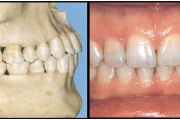

Esimese jäävmolaari ektoopiline lõikumine

Ravijärgne seis. Jäävhammas on täielikult lõikunud.

) Röntgenülesvõte. Ülemise esimese jäävmolaari lõikumine on takistatud 2. piimamolaari tõttu